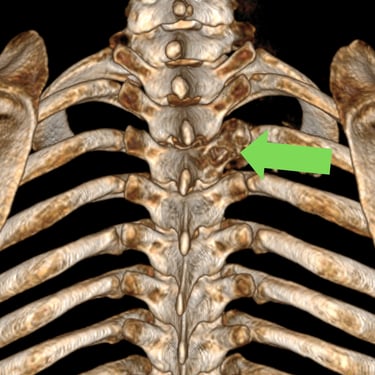

Tumor vertebral dorsal hemorrágico: descompresión medular, biopsia y artrodesis dorsal

El tumor vertebral dorsal puede ocasionar compresión de la médula espinal, dolor intenso y alteraciones neurológicas progresivas. En algunos casos, estos tumores presentan componente hemorrágico que incrementa la presión sobre las estructuras nerviosas. El tratamiento quirúrgico puede incluir descompresión medular para liberar la médula espinal, toma de biopsia para establecer el diagnóstico histopatológico y artrodesis dorsal con instrumentación para estabilizar la columna vertebral. Este abordaje permite reducir el riesgo de daño neurológico, aliviar los síntomas y mantener la estabilidad vertebral. La cirugía se realiza con técnicas especializadas que buscan preservar la función neurológica y mejorar la calidad de vida del paciente.